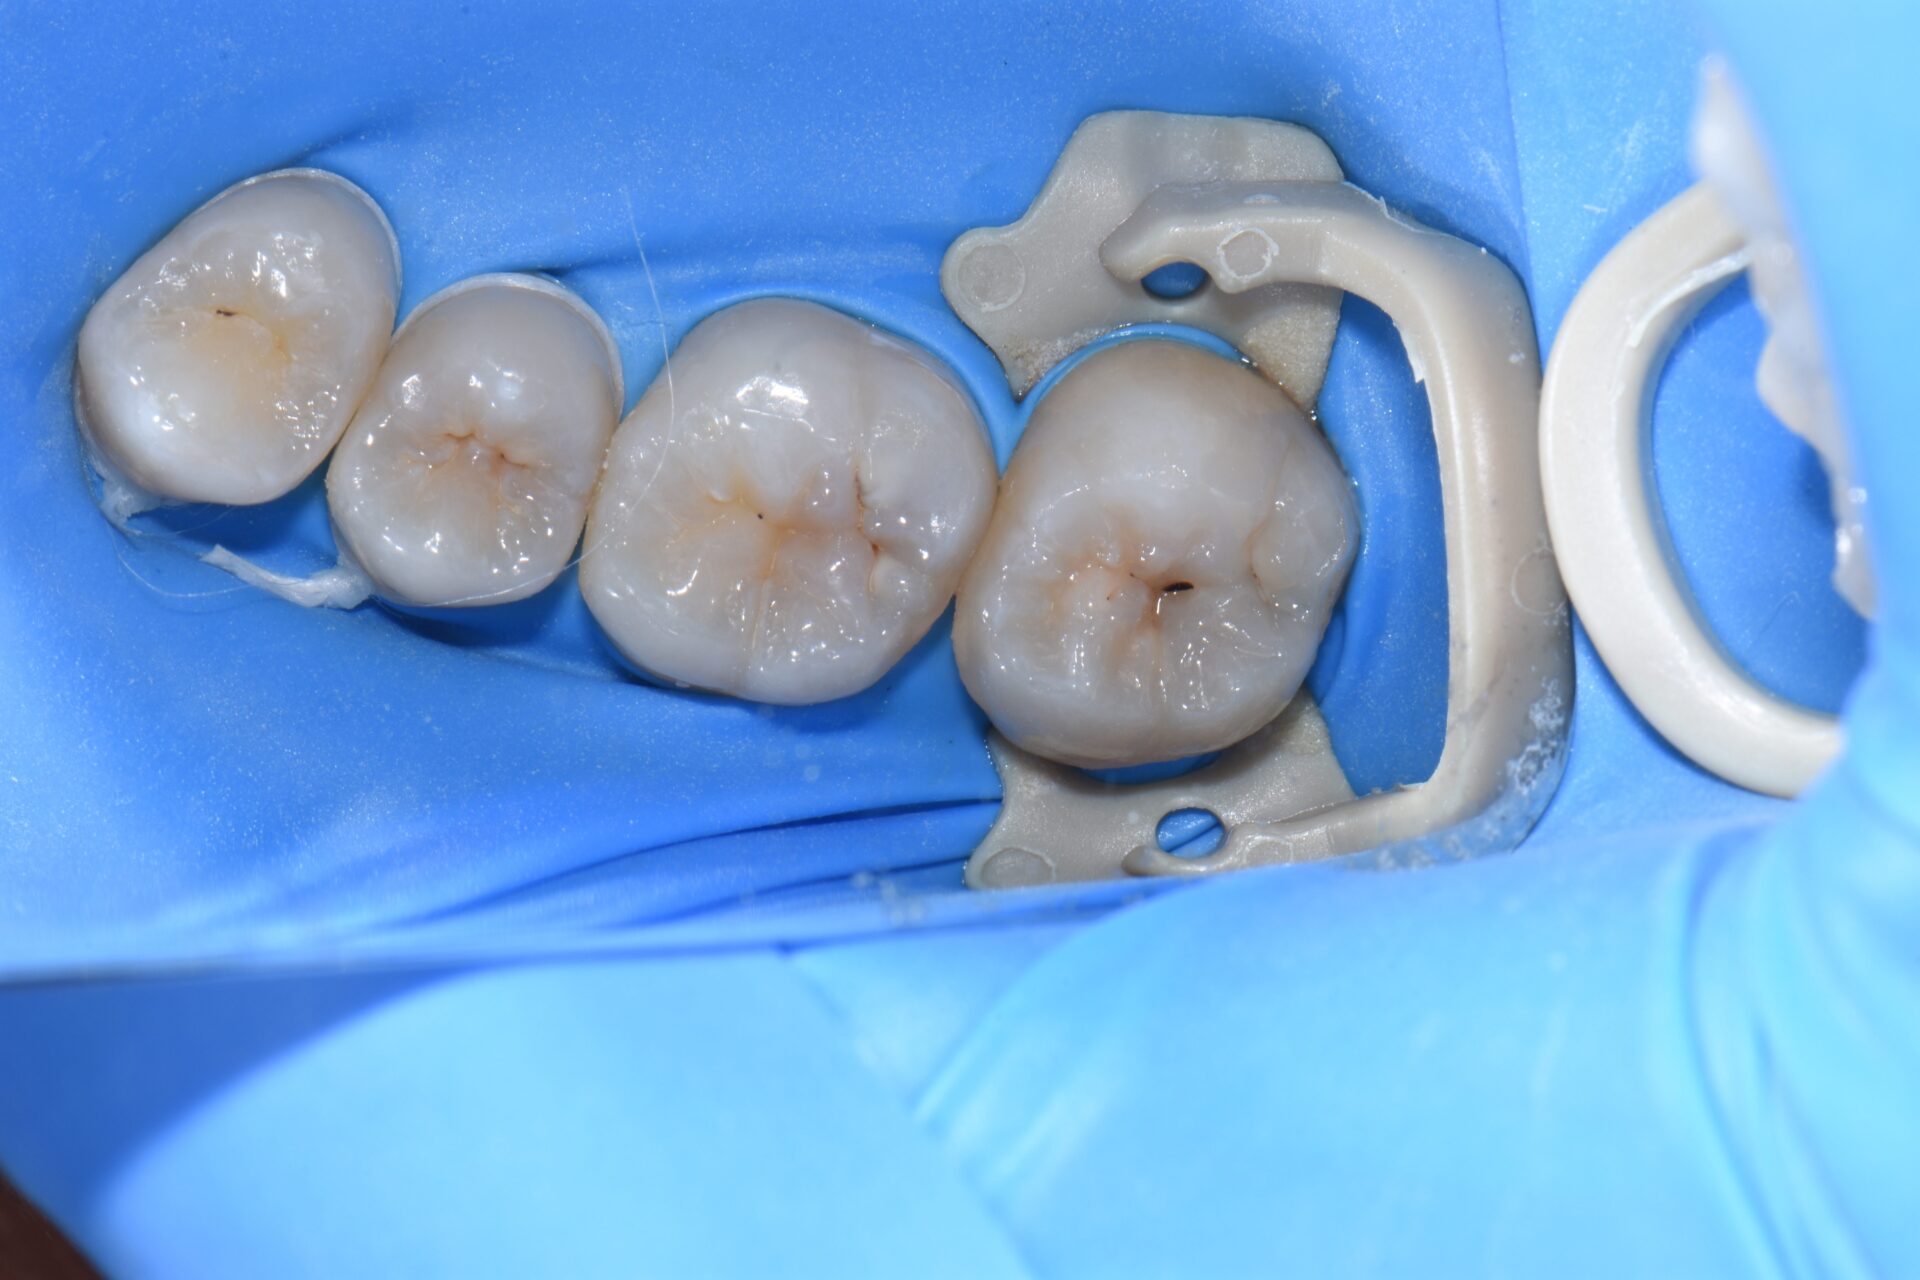

術前 歯科健診と歯のクリーニングで来院。第二大臼歯に虫歯が見つかりました。

無自覚無症状で大変小さな虫歯に見えますが実は大きな虫歯です。

術中 虫歯を除去していくと